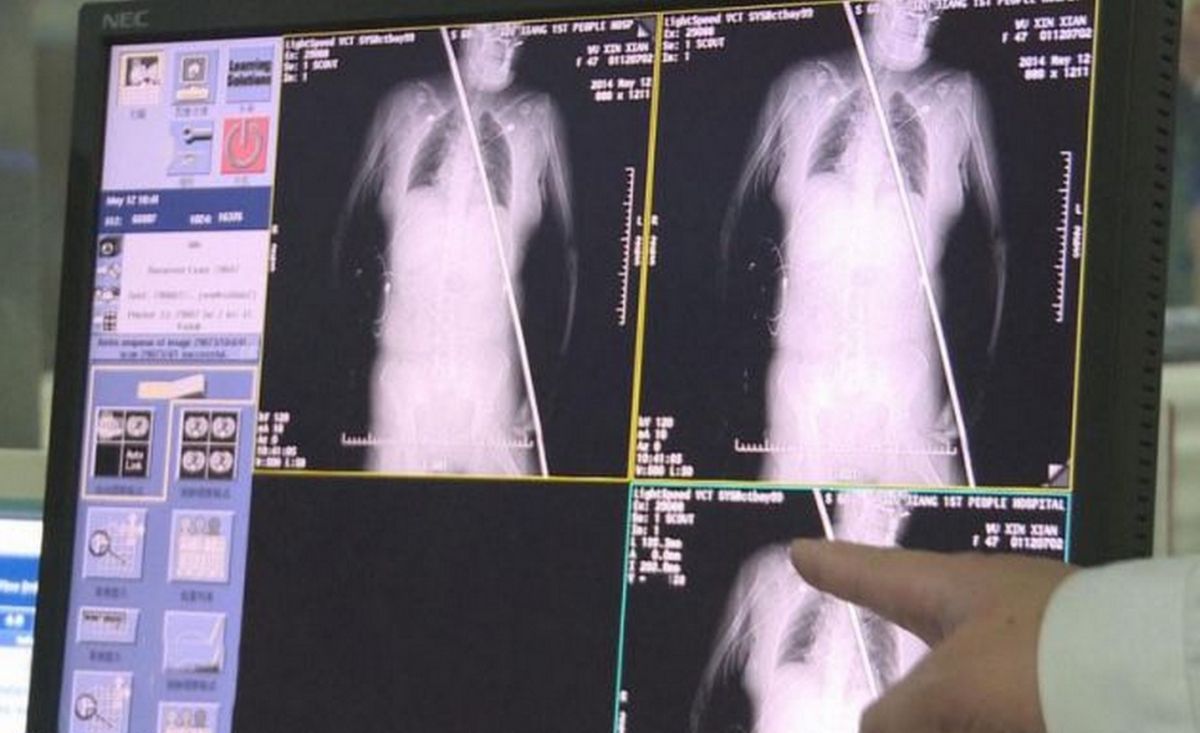

Wu je v mestu Jiujiang padla na dvometrsko jekleno palico, ki ji je predrla levo stegno, šla skozi njen želodec in prsni koš ter izstopila pri vratu. »Nisem vedela, da me je prebodla jeklena palica. Čutila sem le, da mi nekaj štrli iz vratu,« je povedala Wu. »Ko so mi ljudje povedali, da me je prebodla, se nisem upala premakniti.«

Preden so jo prepeljali v bolnišnico, je že padla v komo. Operacija je trajala pet ur in če ne bo prišlo do vnetja, je zelo verjetno, da se bo izmazala. Rešilo jo je, da je bila ves čas pri miru, so povedali kirurgi, sicer bi kaj lahko prišlo do notranjih krvavitev.